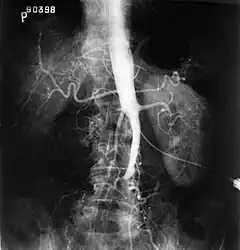

Plate from Gray's Anatomy showing the abdominal aorta and the common iliac arteries.

Fluoroscopic image of an affected aorta

Angiography provides important information regarding the perfusion and patency of distal arteries (e.g. femoral artery). The presence of collateral arteries in the pelvic and groin area is important in maintaining crucial blood flow and lower limb viability. However, angiography should only be used if symptoms warrant surgical intervention.[8]